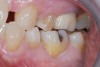

After the patient was anesthetized, the failing alloy restoration was removed along with the recurrent decay. A buildup was placed using bulk-fill composite and an adhesive bonding agent. Following preparation (Figure 4 and Figure 5), a No. 1 cord was placed in the sulcus, and then the preparation, working quadrant, opposing quadrant, and bite were scanned using an intraoral scanner.

(4.) Preparation.

Figure 4

(5.) Preparation.

Figure 5